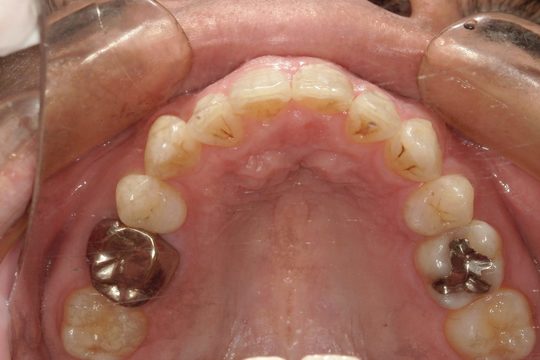

Y.S. 30代男性

全体的にガタガタしているのが気になるという主訴だったため、上下左右第一小臼歯を抜歯し、叢生を並べました。

治療の期間:R3. 9/1〜R5. 10/31

治療の価格:88万円